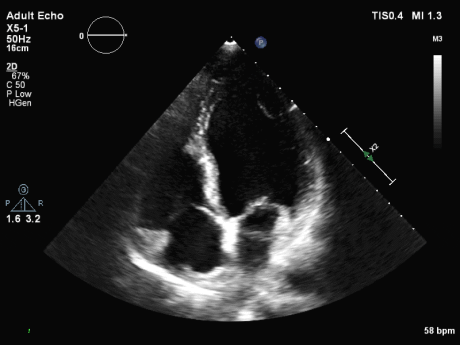

图(1)

图(2)

冠脉CTA:左前降支近端多发软硬斑块形成,管腔狭窄约80%。